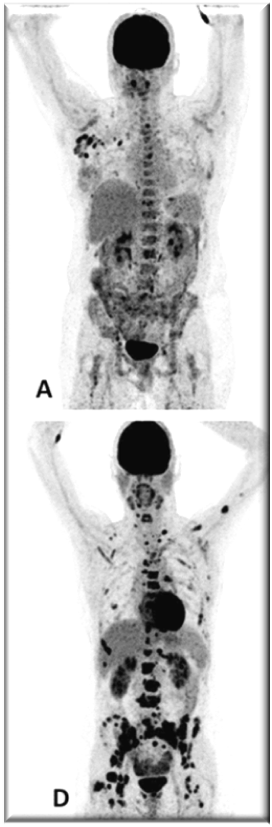

PET images of two patients with metastatic invasive lobular carcinoma responding (A-C) and not responding (D-F) to palbociclib + letrozole

Adapted with permission from Boers, J., et al. European Journal of Cancer. 2020; 126: 11-20

Upper row responder: (A) Baseline [18F]FDG-PET shows pathological uptake in axillary lymph nodes (right side) and in nearly all vertebrae and pelvic bones. (B) Baseline [18F]FES-PET with pathological ER expression in the axial skeleton (vertebrae, pelvic bones, proximal humeri and femora) and in axillar lymph nodes. (C) [18F]FDG-PET after 8 weeks shows almost complete metabolic response. The patient has been on treatment for more than 70 weeks.

Lower row non-responder: (D) Baseline [18F]FDG-PET shows pathological uptake in multiple skeletal lesions. (E) Baseline [18F]FES-PET with only some increased ER expression in thoracic vertebrae. (F) [18F]FDG-PET after 8 weeks shows no metabolic response, with some increase in the pathologic uptake in the multiple skeletal lesions.